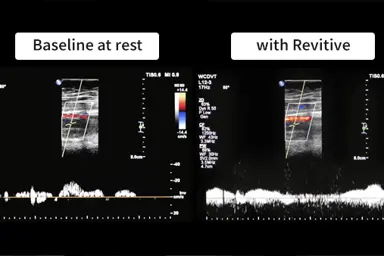

Clinical Tests Prove How Well Revitive Works

After only 10 minutes of using the Revitive Circulation Booster, all symptoms were significantly improved.